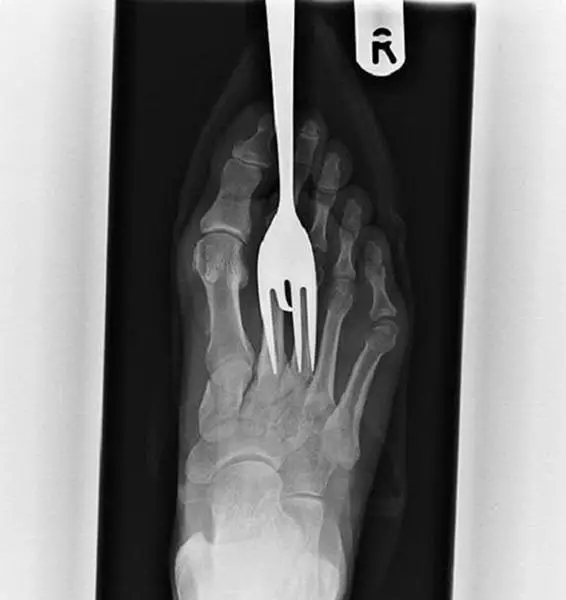

x光照片 异物

x光检查阻塞性异物这5个技巧你掌握了吗

x光片里的体内异物简直大开眼界

x光下的人体异物盘点好奇他们都是怎么进去的

打好针,回到骨科急诊室,大夫在电脑上调出x线片,告诉我异物扎穿了中指

x光照射下人体内15个奇葩物体第9个太恐怖

出奇:x光下的异物入体

盘点x光透视下的人体异物,太惊悚了,看着都痛!__财经头条